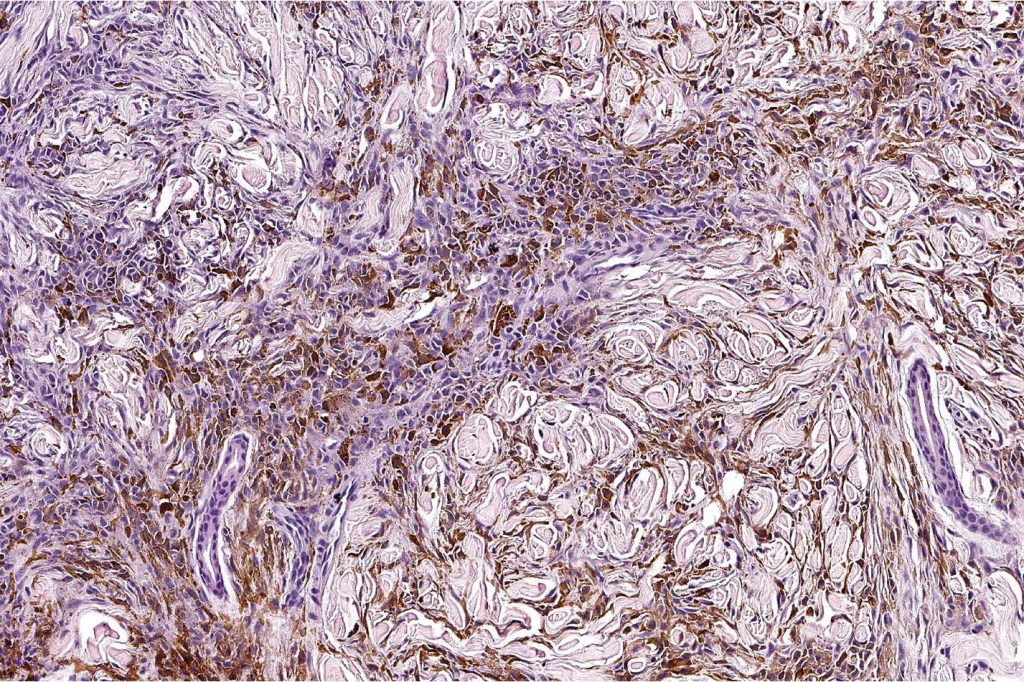

Combined common melanocytic nevus and pigmented epithelioid melanocytoma